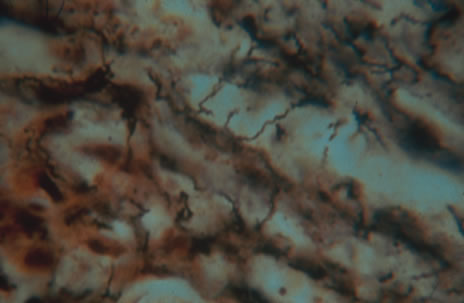

The gold standard for diagnosis of intraocular tuberculosis is demonstration of acid-fast bacilli in fluid or tissue sample either by direct smear and culture, polymerase chain reaction (PCR) or ELISA (Fig. 17). A screening test such as the Mantoux test is useful but is less specific and must be interpreted based on the size of induration in correlation with socioeconomic status, immune status, and contact history of the patient. The test consists of an intradermal injection of purified protein derivative (PPD) from tubercle bacilli. Systemic sensitization to this protein occurs several weeks after primary infection. At 48 to 72 hours postinjection, skin induration larger than 5 mm in an HIV-positive patient or patients with a positive chest x-ray that are previously untreated, larger than 10 mm in other high-risk populations, and larger than 15 mm for healthy patients with low risk factors are considered significant. A positive reaction may persist in the absence of clinically active disease and therefore must be correlated with chest radiography and symptomatology.

Fig. 17. Acid fast bacilli are present in the biopsy of a lesion.